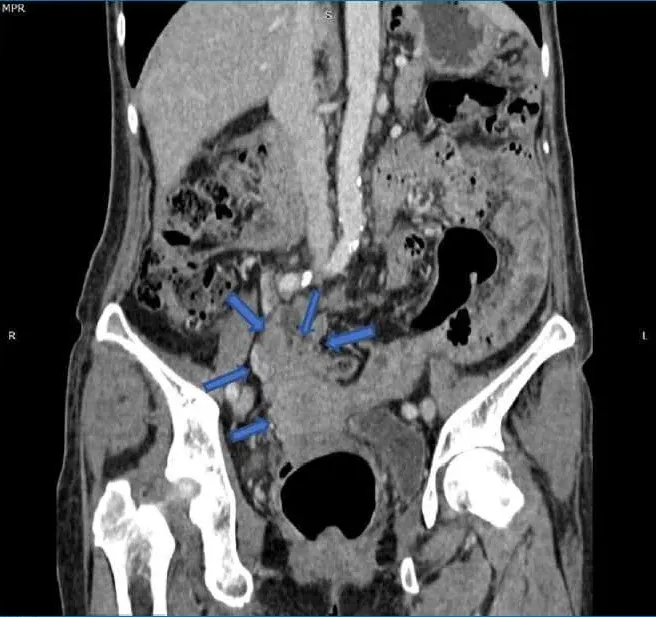

她第一次就诊时的常规胸片(图1)检查偶然发现了右肺肿块。随后的胸部增强计算机断层扫描(CT)(图2)显示肺右下叶后基底段的肺肿块大小为4.7×7.0×7.0 cm(前后×宽度×头尾)。肿块附近也有卫星结节。对肿瘤进行支气管镜活检,组织病理学检查(HPE)结果显示腺癌,证实为原发性肺恶性肿瘤,表皮生长因子受体(EGFR)基因的外显子19缺失。

图1. 胸部X线,右下肺叶有肿块